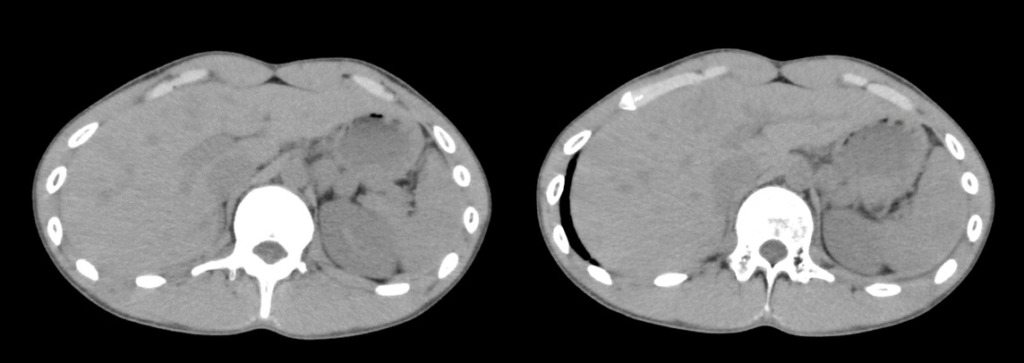

実際のCT画像です。

撮影された腹部単純CTでは、一見すると明らかな骨折や活動性出血、臓器損傷は指摘されませんでした。

しかし、血液検査の結果で肝酵素の上昇を認め、改めて画像を詳細に確認したところ、肝臓のS4領域にわずかな低吸収域(周囲より黒い部分・↓赤丸部分)が認められました。